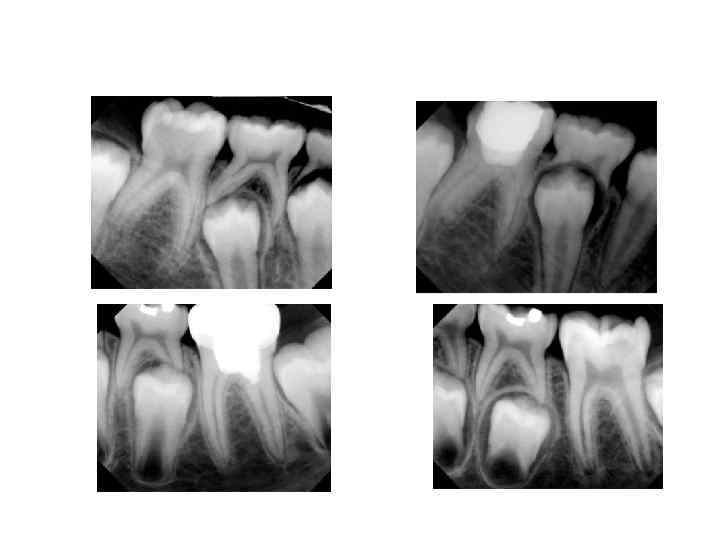

Рентгенологические стадии минерализации коронки: 1. Стадия черепков (жевательные зубы) или полоски (резцы); 2. Стадия кольца; 3. Стадия колпачка.

Рентгенологические стадии минерализации корня. 1. Рост корня в длину; 2. Стадия несформированной верхушки; 3. Стадия незакрытой верхушки.